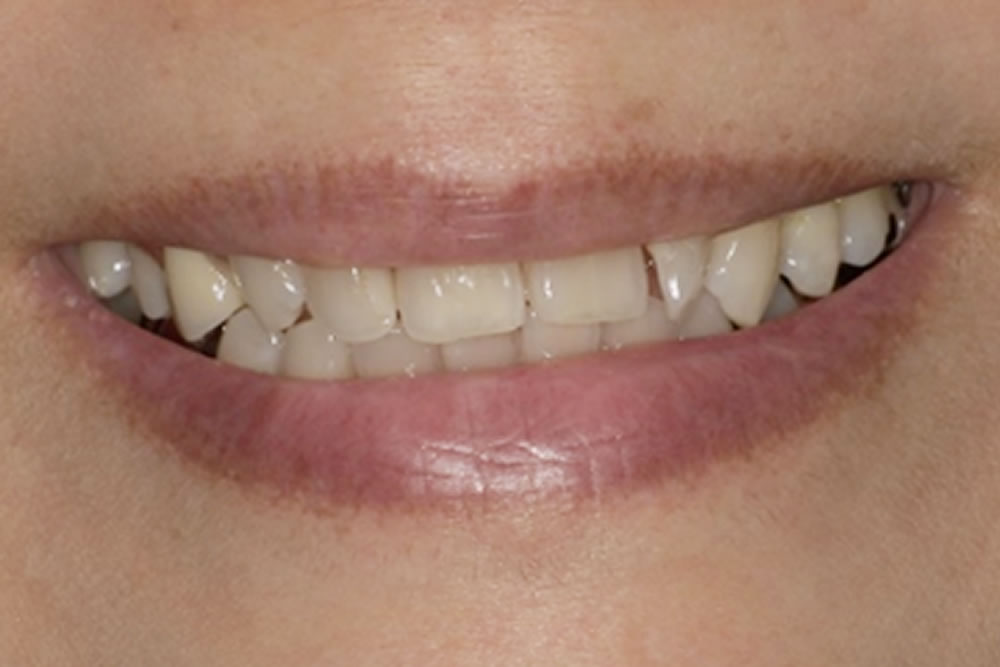

ミラクルデンチャー症例123(60代 女性)

製作したミラクルデンチャー